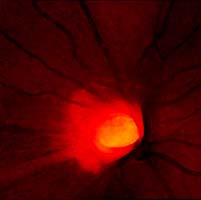

Očekávali byste protažení exkavace k hornímu pólu terče, jak nám ukazuje tento snímek z tomografu HRT II.

exkavace levé oko

Na kterém oku je exkavace větší, na pravém nebo na levém? Podle pohledu na fotografie jistě na levém.

exkavace pravé oko

Na kterém oku je exkavace větší, na pravém nebo na levém? Podle pohledu na fotografie jistě na levém.

Co je příčinou toho, že při pohledu na snímky hodnotíme rozsah exkavace nesprávně? Je to skutečnost, že i růžová oblast neuroretinálního lemu může být již prohloubená, což vídáme zvláště na počátku rozvoje glaukomové neuropathie.